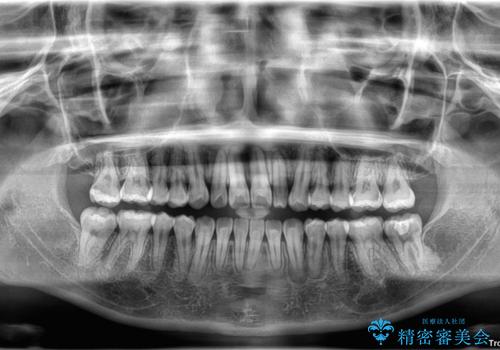

- 患者様は「歯並び全体のデコボコが気になり、人前で笑うことに抵抗がある」とのことでご来院されました。

診査の結果、上下顎ともに叢生が認められましたが、ワイヤー矯正・マウスピース矯正のいずれでも対応可能な症例でした。

という患者様のご希望を踏まえ、プラスチックブラケット+コーティングワイヤーを用いたワイヤー矯正を選択しました。